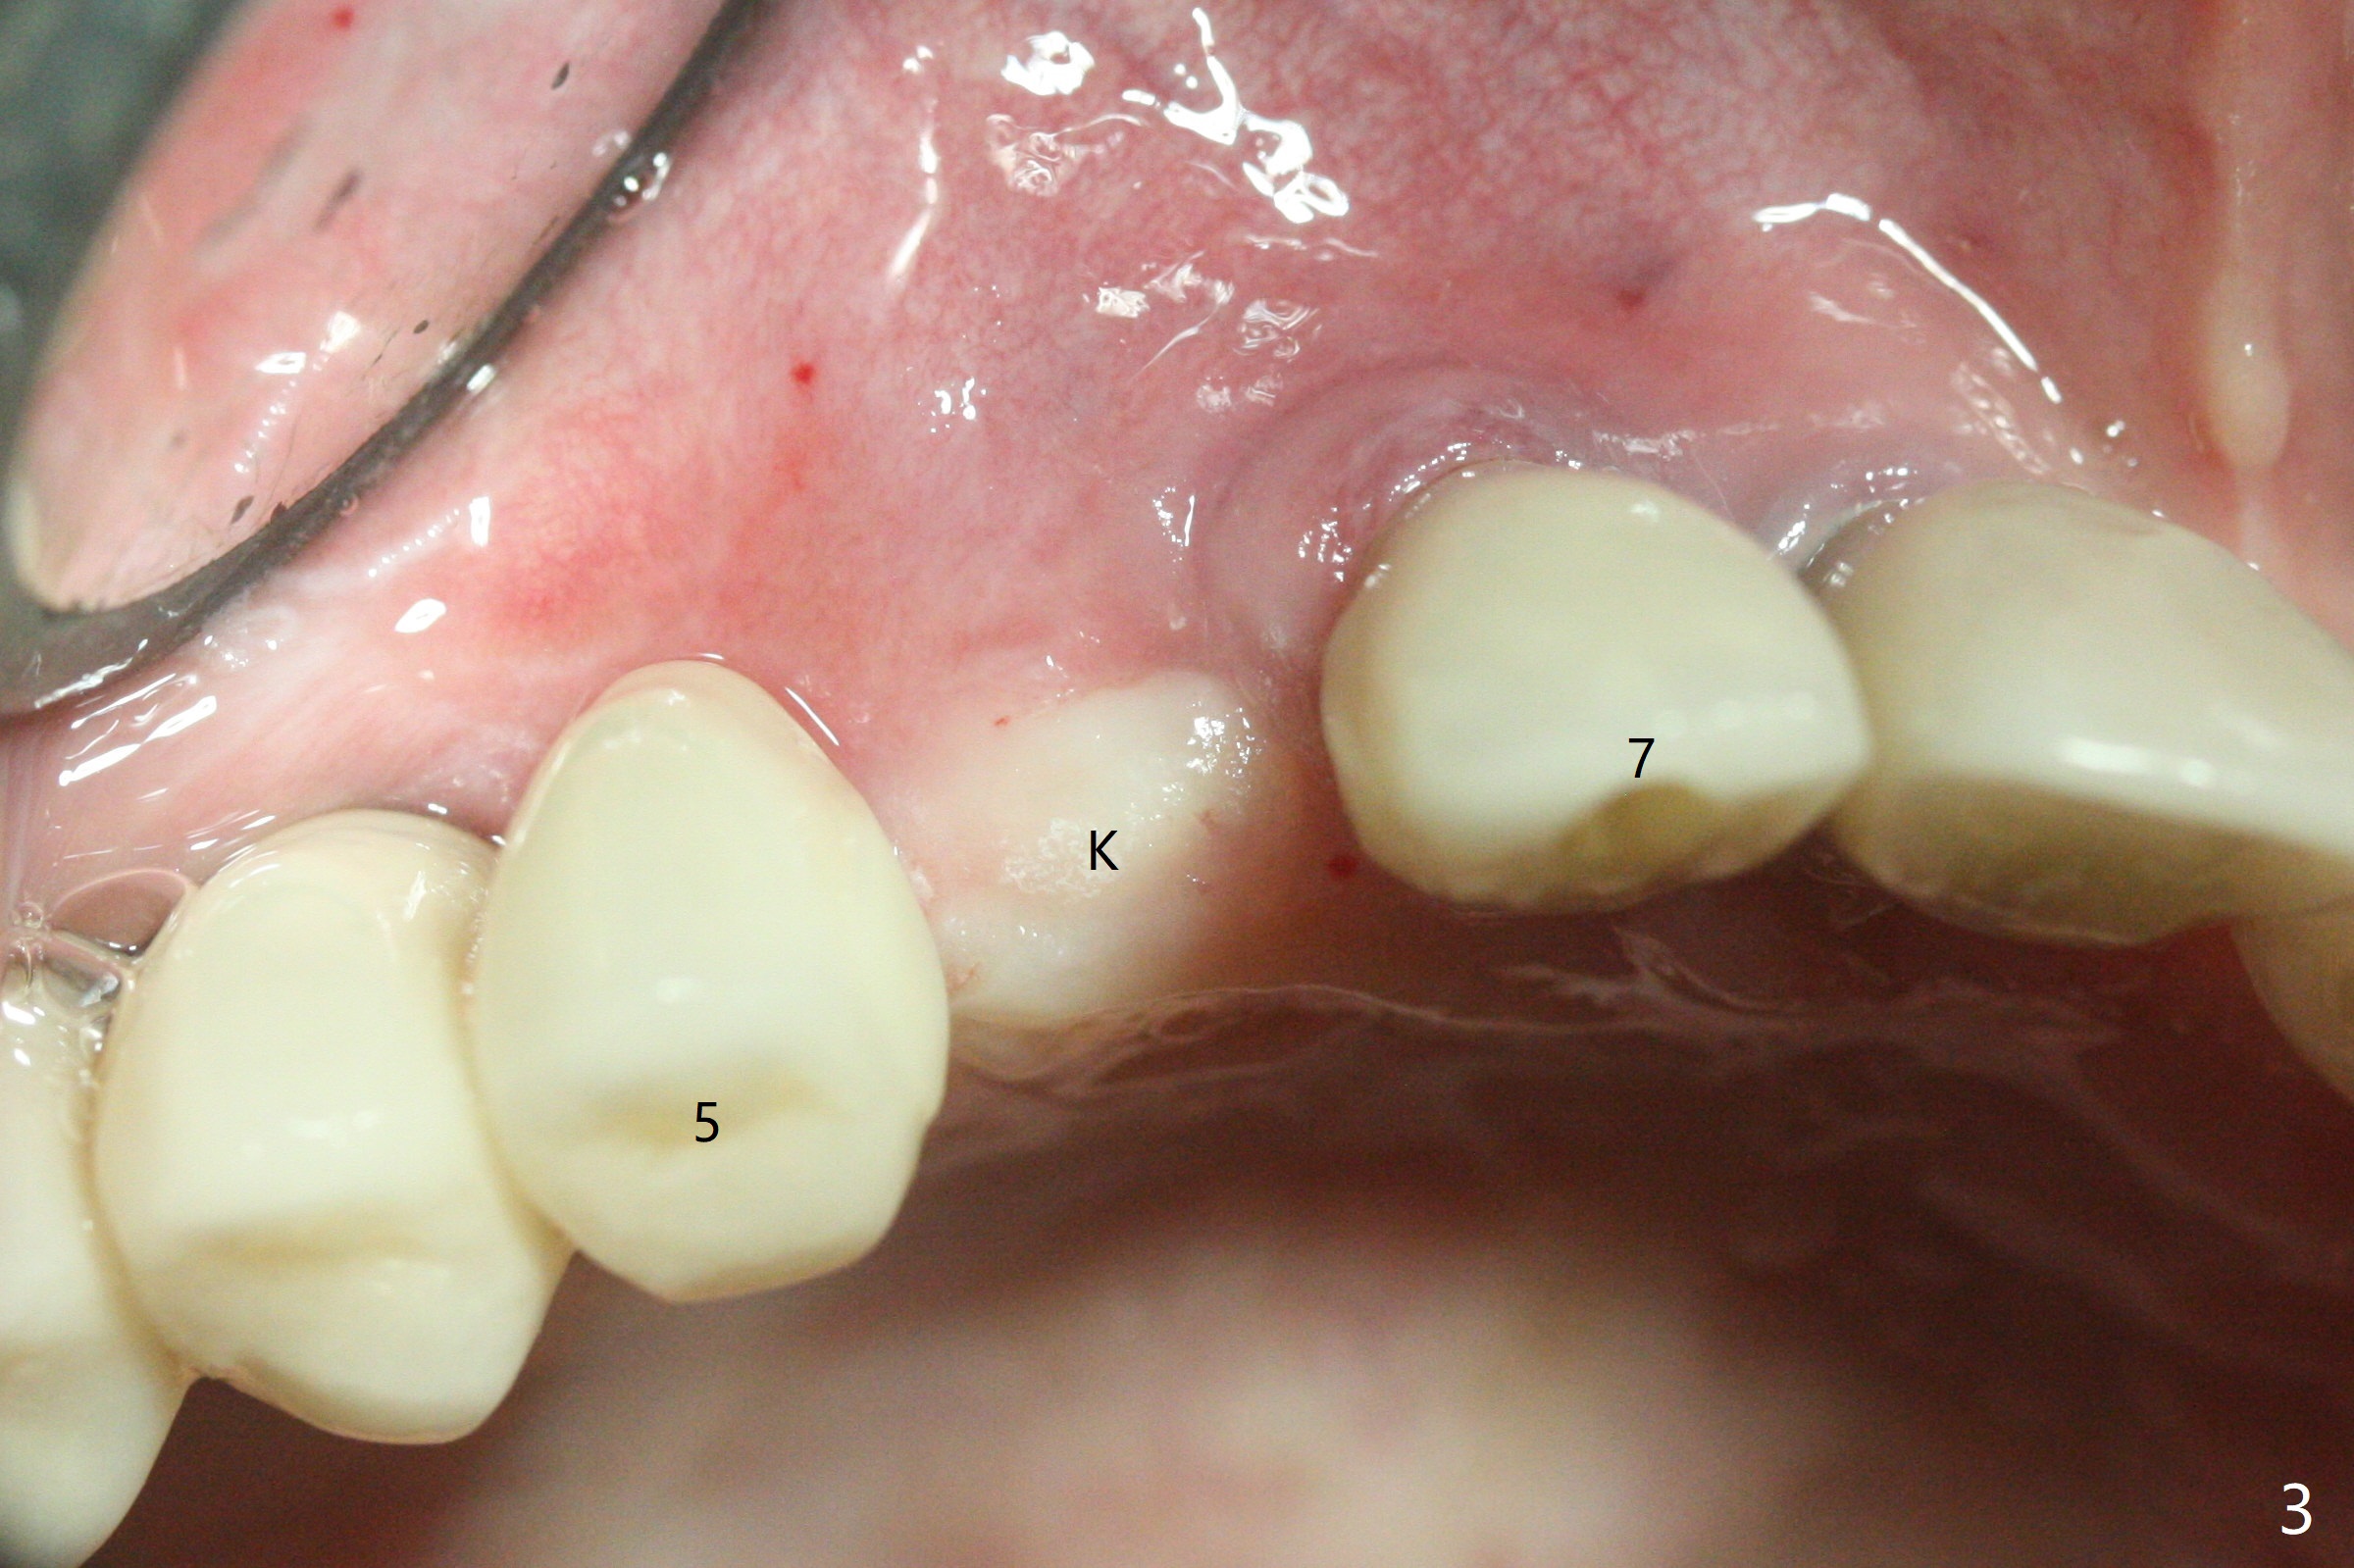

64岁女3-7牙桥,7号牙植体颊侧牙龈缘红肿(图一:*),脓液(图二:^),需要切开清洗,但是6号牙桥墩颊侧非角化龈(N)妨碍切口,所以必须去除桥墩,暴露牙槽嵴顶角化龈(图三:K),容易切开,最后缝合而不容易出血,伤口容易愈合。切开清创后重大发现是牙冠边缘(图四:^)直接接触植体微螺纹,没有基台与牙龈之间形成的屏障,有利于口腔细菌直接感染植体。直感告诉术者必须缩短牙冠边缘,抛光。然后缺损处放置粘性骨粉(图五,八:S,与图七(术前)比较),表面覆盖PRF膜,缝合(图六)。准备术后尽早去除牙冠,预防细菌再次感染。并且在6号牙位植入2x8.5毫米植体。